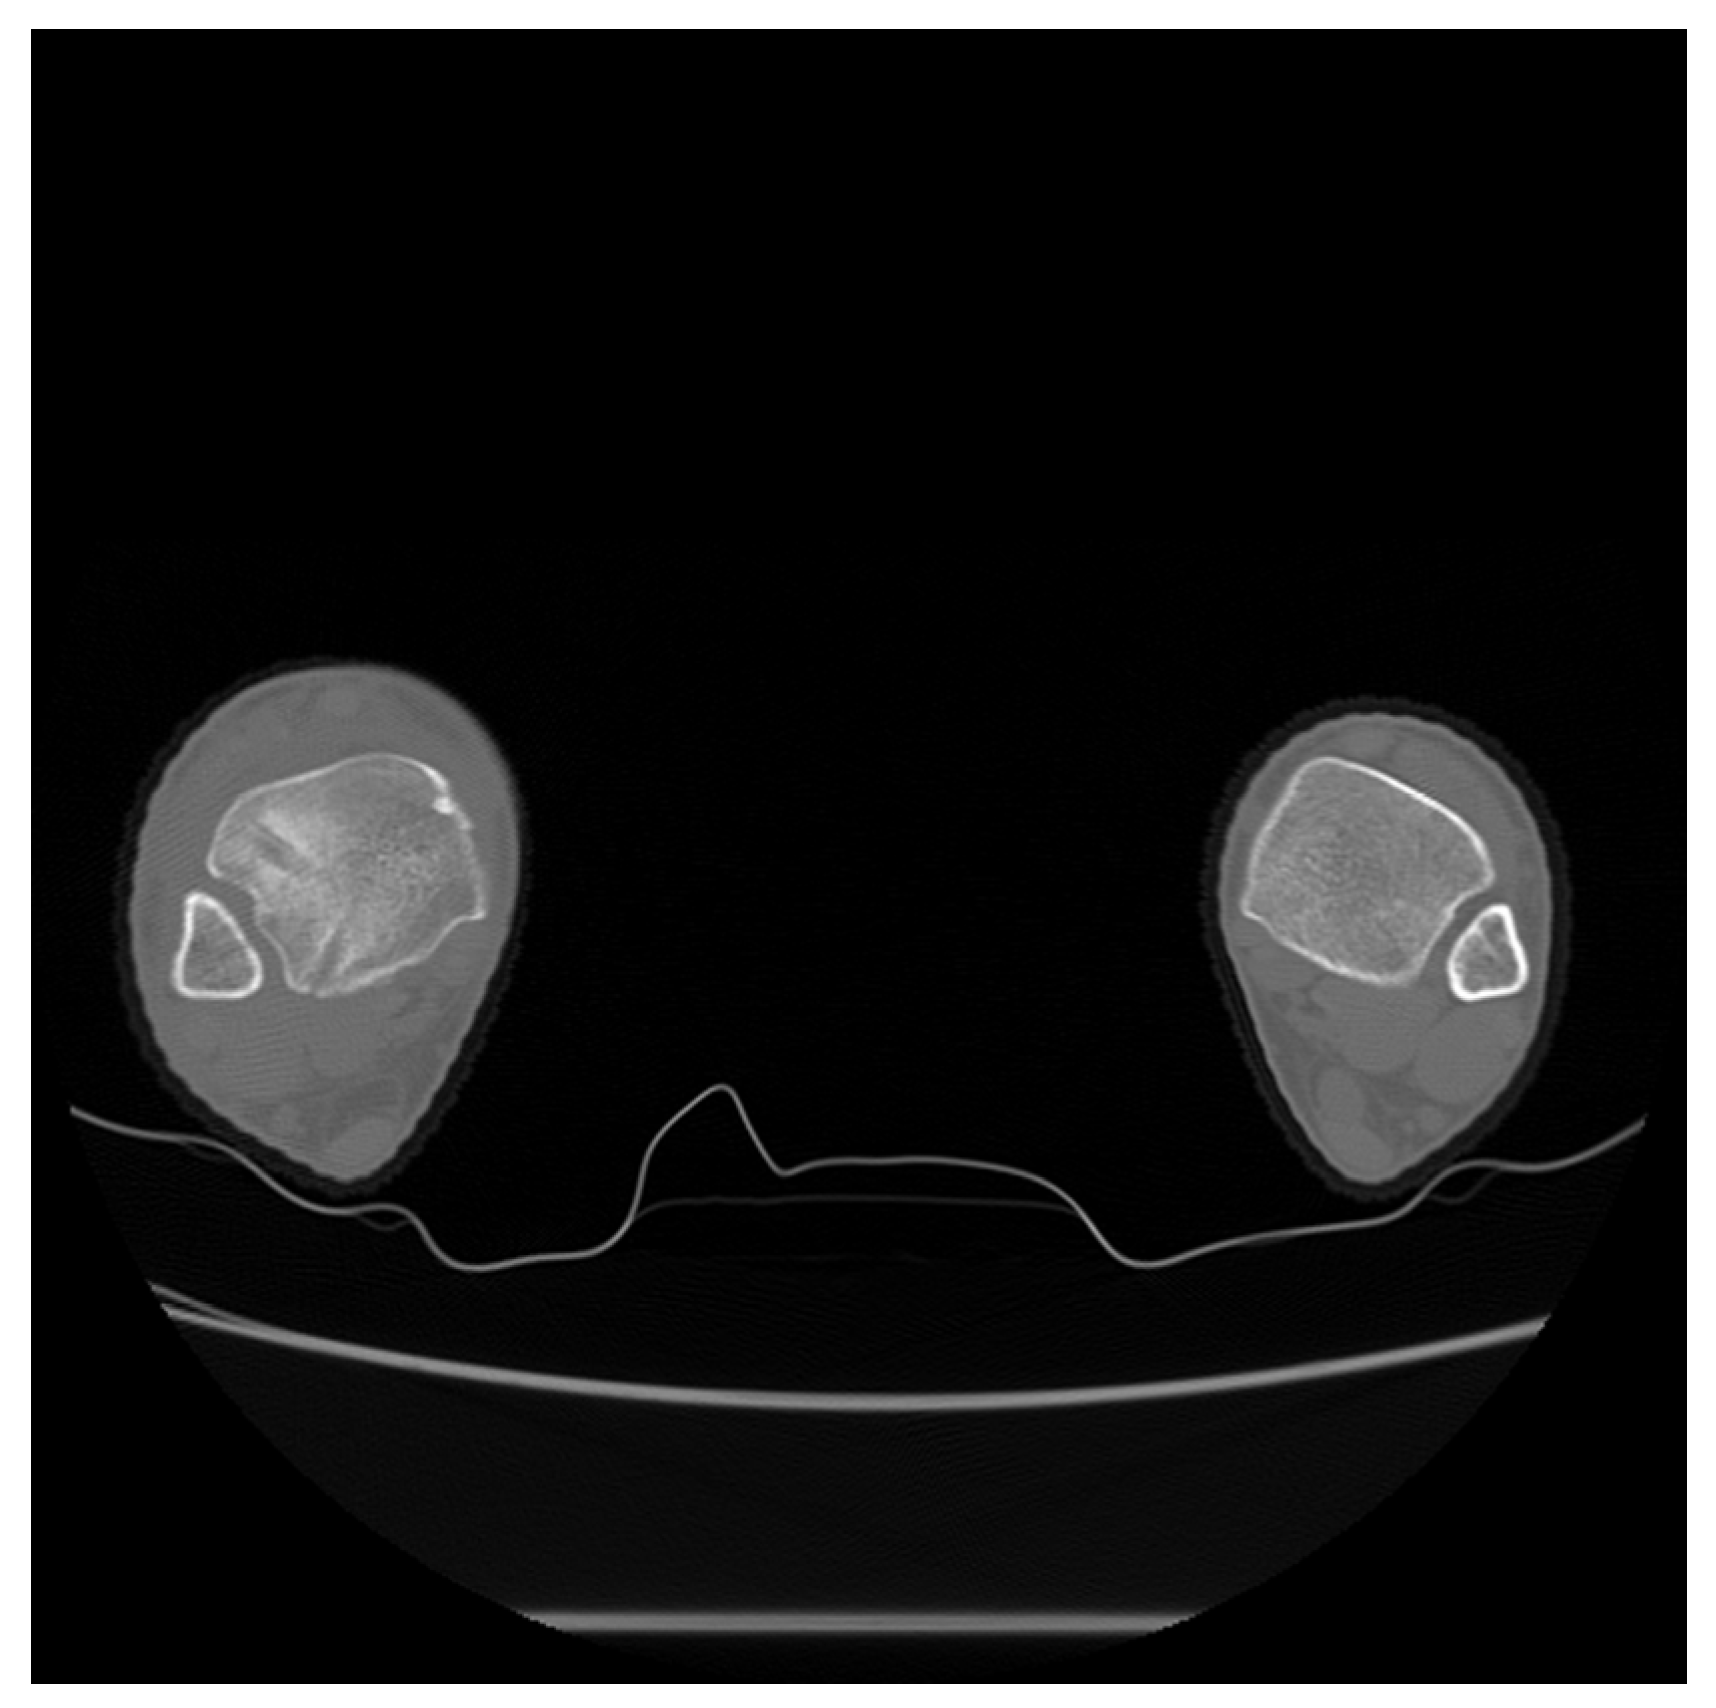

2. Case Presentation